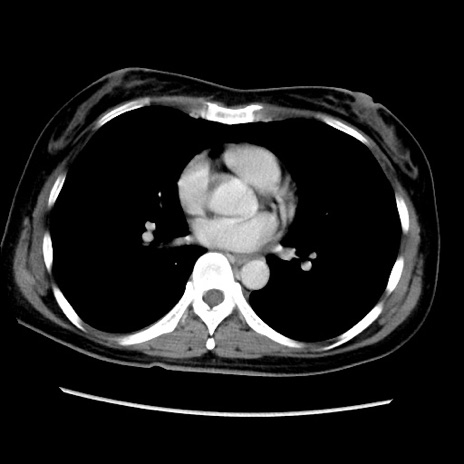

症例39(横断像)

【症例】40歳代女性

【主訴】上下腹部痛

【現病歴】2日目から下腹部痛あり。夜間は痛みで眠れなかった。昨日より上腹部痛と下痢が出現。臥位で痛みは軽快したため、休んでいた。本日になって臥位でも立位でも痛みが強くなってきたため救急要請。

【既往歴】子宮内膜症

【身体所見】部:平坦・軟、左上下腹部に圧痛あり、反跳痛あり。

【データ】WBC 21800、CRP 26.78